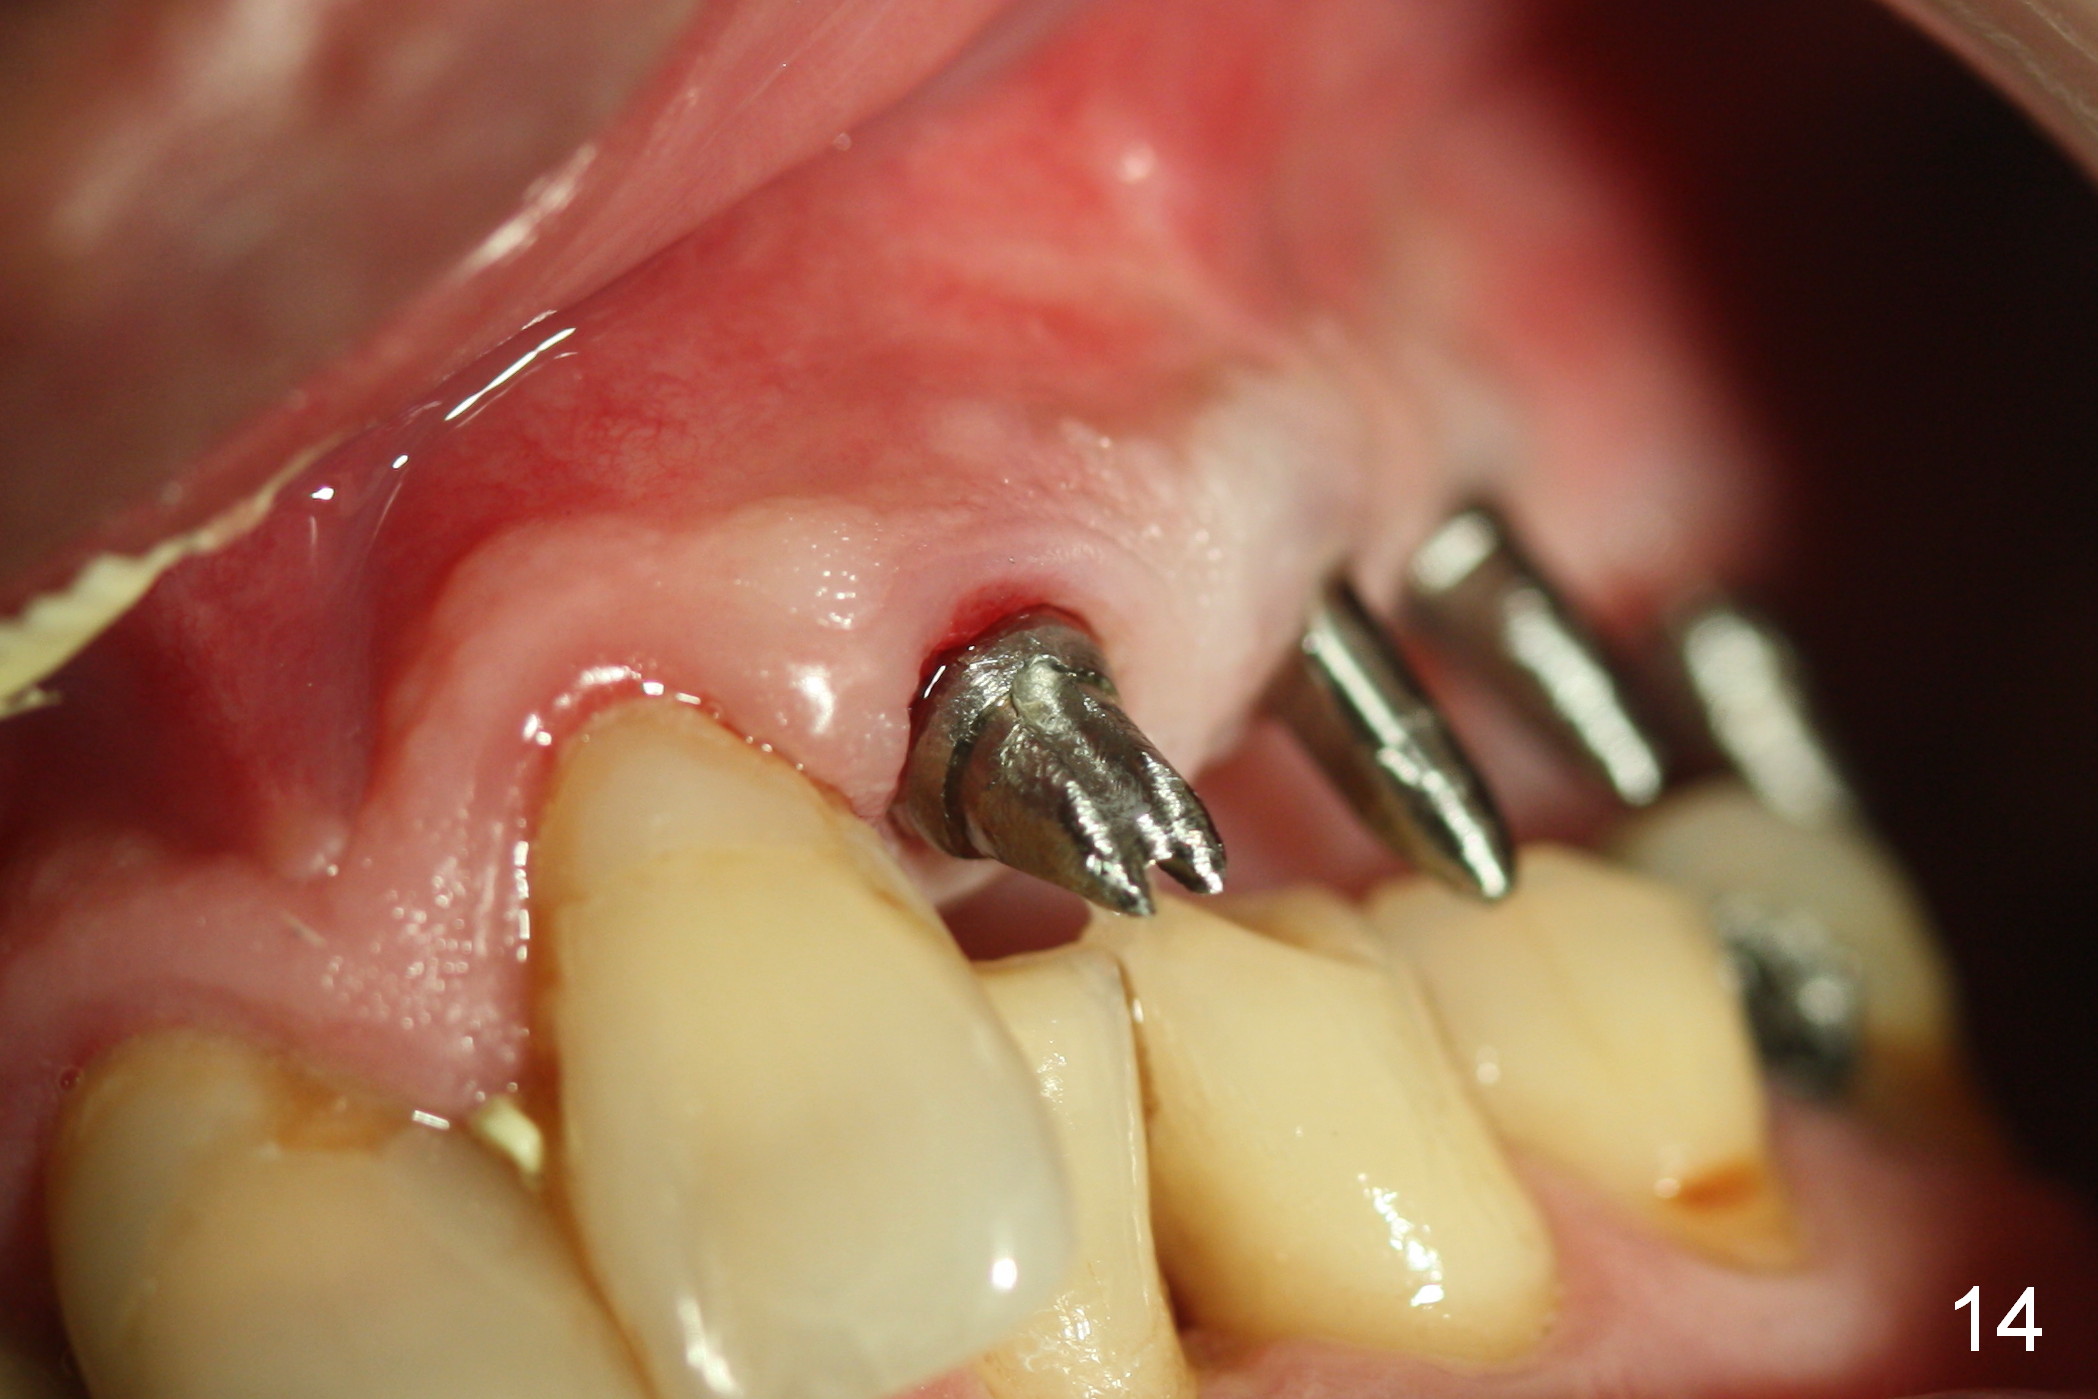

The patient returns for final restoration 3.5 months postop; it appears that the implants have osteointegrated (Fig.12,13).  After reprep, there is no gross buccal plate atrophy at #10 (Fig.14).